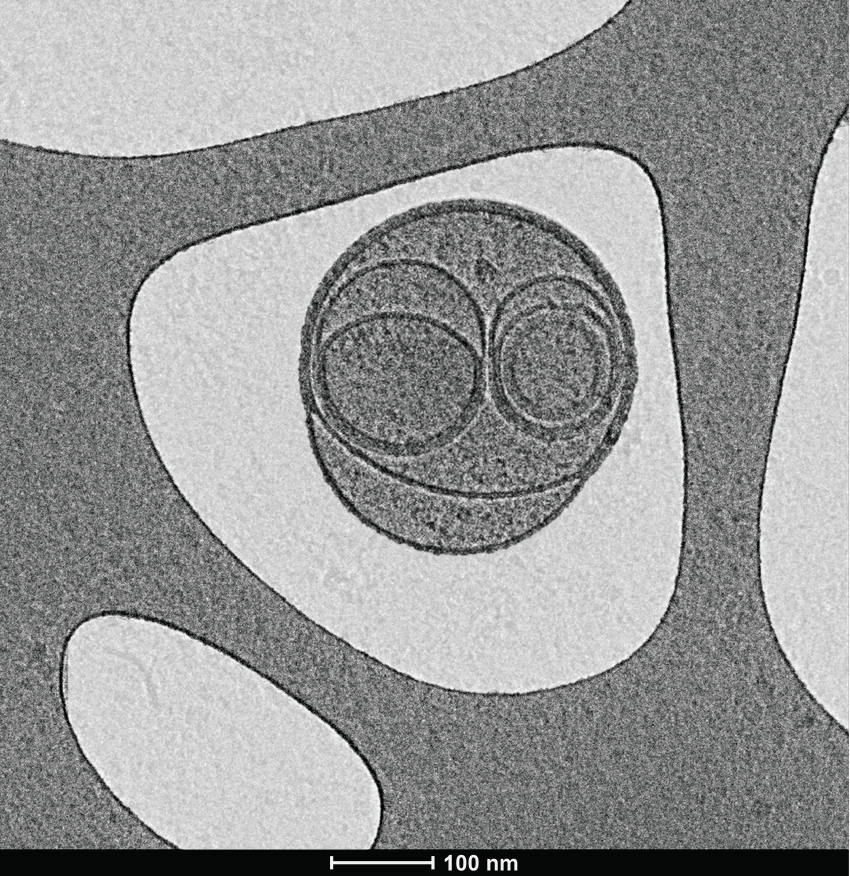

A cryogenic electron microscopy image of extracellular vesicles, resembling a smiley face, within the holes of a perforated support film. The background was artificially shaded light gray to highlight the vesicles.

Wolfram Laboratory